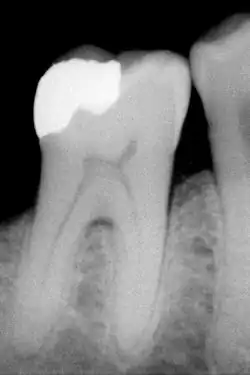

The large amount of mineral in enamel accounts not only for its strength but also for its brittleness.[6] Tooth enamel ranks 5 on Mohs hardness scale (between steel and titanium) and has a Young's modulus of 83 GPa.[4] Dentin, less mineralized and less brittle, 3–4 in hardness, compensates for enamel and is necessary as a support.[7] On radiographs, the differences in the mineralization of different portions of the tooth and surrounding periodontium can be noted; enamel appears lighter than dentin or pulp since it is denser than both and more radiopaque.[8]

An X-ray showing enamel and dentin replaced by an amalgam restoration

Most dental restorations involve the removal of enamel. Frequently, the purpose of removal is to gain access to the underlying decay in the dentin or inflammation in the pulp. This is typically the case in amalgam restorations and endodontic treatment.